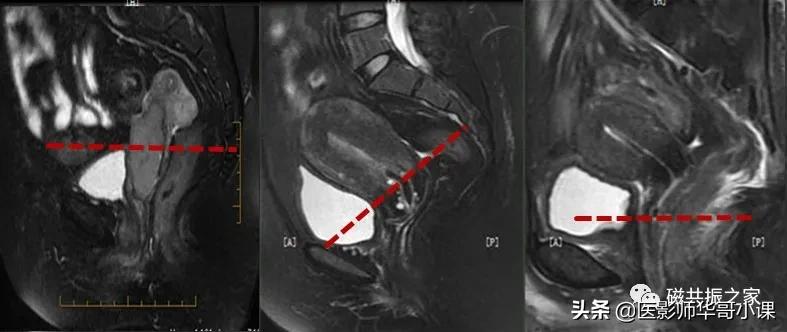

在横轴位和冠状位上定位。在横轴位上找到显示子宫体最大的层面,使定位线垂直于当前子宫内膜长轴,在冠状位上调整角度使定位线平行于子宫全长长轴(平行于子宫颈和子宫底中点的连线);如是宫颈病变,应以宫颈管为基准定位。左右扫描范围包括整个子宫,需包括整个病变范围。

在冠状位和矢状位上定位,在矢状位上找到显示子宫全景最好的层面,如需了解宫颈病变,使定位线垂直于宫颈管长轴(图A),如需了解子宫内膜病变,使定位线垂直于子宫内膜长轴(图B)。在冠状位调整角度使两侧对称扫描,扫描范围上至子宫上缘下至耻骨联合,需包括整个病变范围,如观察转移性病变需加大扫描范围。

在横轴位和矢状位上定位,在矢状位上找到显示子宫全长最好的层面,如需了解宫颈病变,使定位线平行于宫颈管长轴(图A),如需了解子宫内膜病变,使定位线平行于子宫内膜长轴。在横轴位上找到显示子宫最大的层面,使定位线平行于当前子宫内膜长轴,扫描范围包括整个子宫及两侧附件,需包括整个病变范围。